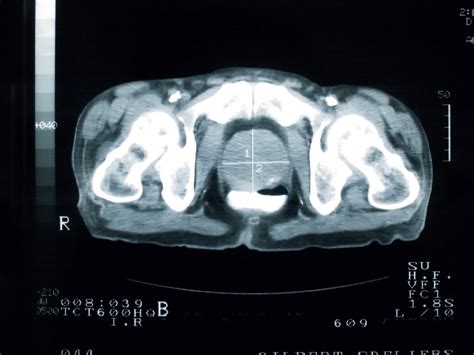

The spine’s curvature—lordotic in the cervical and lumbar regions, kyphotic through the thoracic—serves as a biomechanical masterpiece. Its alignment along the body’s vertical axis governs load distribution, spinal cord protection, and postural stability. The L4-L5 intervertebral disc, often a source of lower back pain, sits at the optimal level where compressive forces peak; misalignment here shifts stress to adjacent segments, accelerating degeneration.

Beyond static alignment, the spine’s *segmental* positioning—each vertebra’s interplay with vertebral bodies, facet joints, and ligamentous complexes—dictates nerve root function. A single misaligned vertebra, such as a subluxation at C5, can impinge on the cervical spinal nerve, triggering pain, numbness, or motor deficits. Modern imaging reveals that optimal spinal positioning preserves intervertebral hydration and disc height—critical for shock absorption in high-impact activities.

Hidden mechanics: The vertebral canal’s 12-degree anterior tilt, combined with the sacrum’s 25-degree angle relative to the pelvis, creates a neutral zone that shelters the spinal cord from vertical shock. This alignment is not fixed—it adapts subtly to movement, with intravertebral discs shifting up to 3 millimeters during flexion.